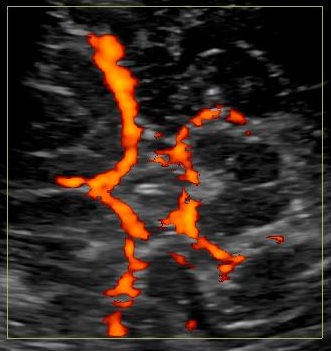

Brain death can be confirmed with ancillary tests such as Nuclear Medicine, EEG and TCD.

On TCD you’ll encounter doppler signals that have sharp systolic spikes and no diastolic flow. Later on reversal of flow occurs. 2 scans separated by 30 minutes should be performed.